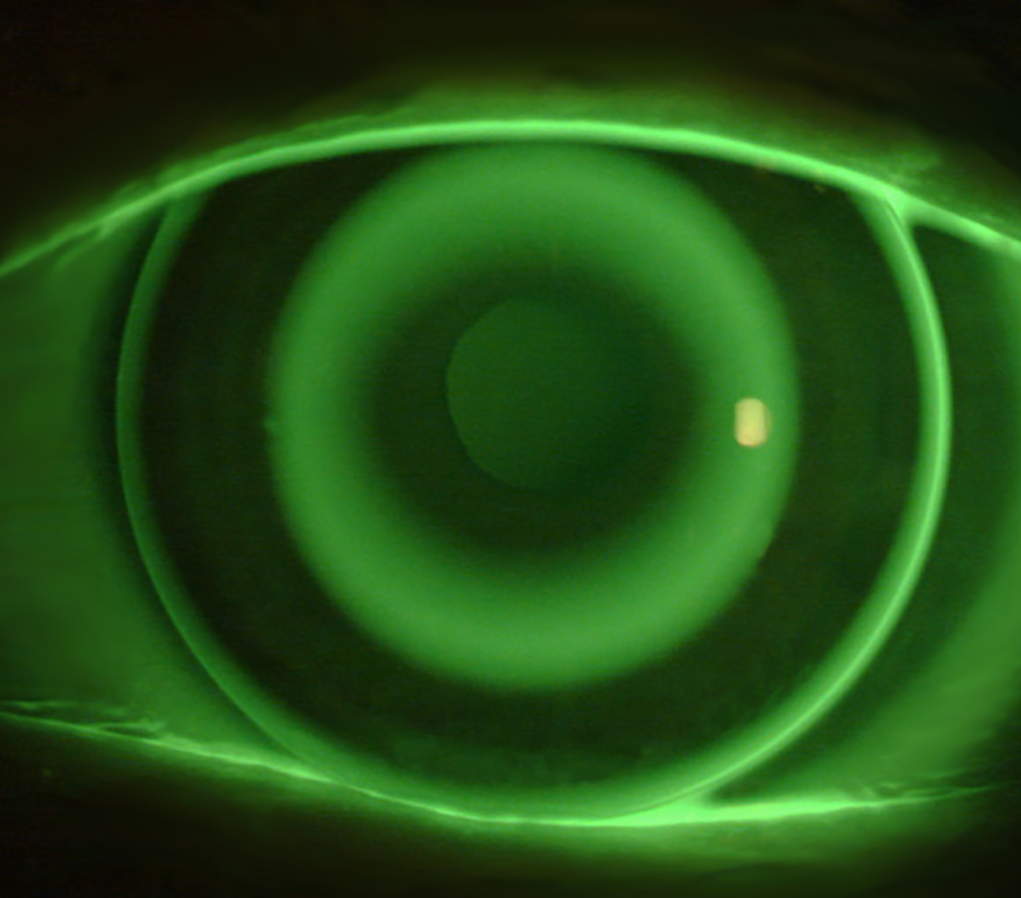

- Jak ocenić dopasowanie soczewek ortokorekcyjnych

- Jak analizować mapy rogówki pod kątem soczewek ortokorekcyjnych?